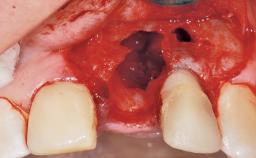

Placement Protocol Immediate implant placement

Socket Morphology Single-root socket

Socket Integrity Damage to one or more bone walls

Bone Volume Damage to one or more socket walls

Complexity Moderate

Risk of Complications High